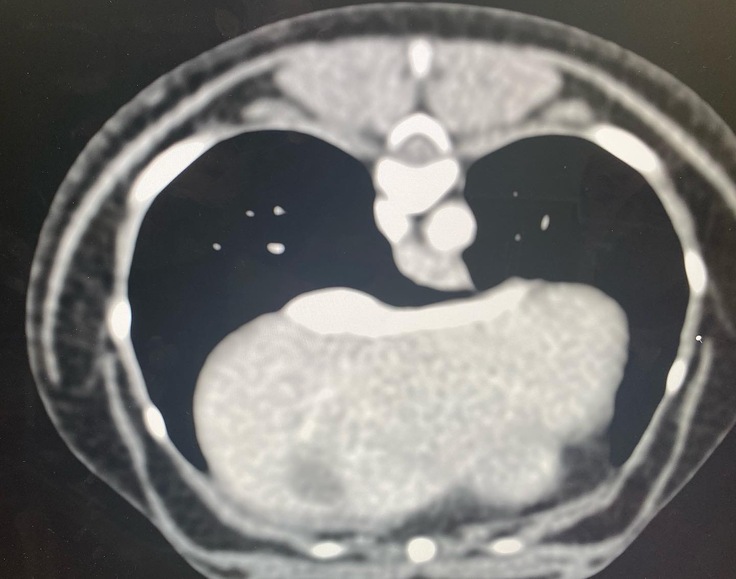

↓この診察内容で門脈体循環シャントを

先生が発見して下さいました。

○↑に載せてある診療明細書の腹部超音波エコー・x線検査の結果

↓CTの結果です

○↑に載せてある全身麻酔によるCT検査CTで2本の太いシャント血管があった事

シェリーの場合はシャント血管2本見つかりました。手術1回の可能性50%2回以上の可能性50%との事でした。